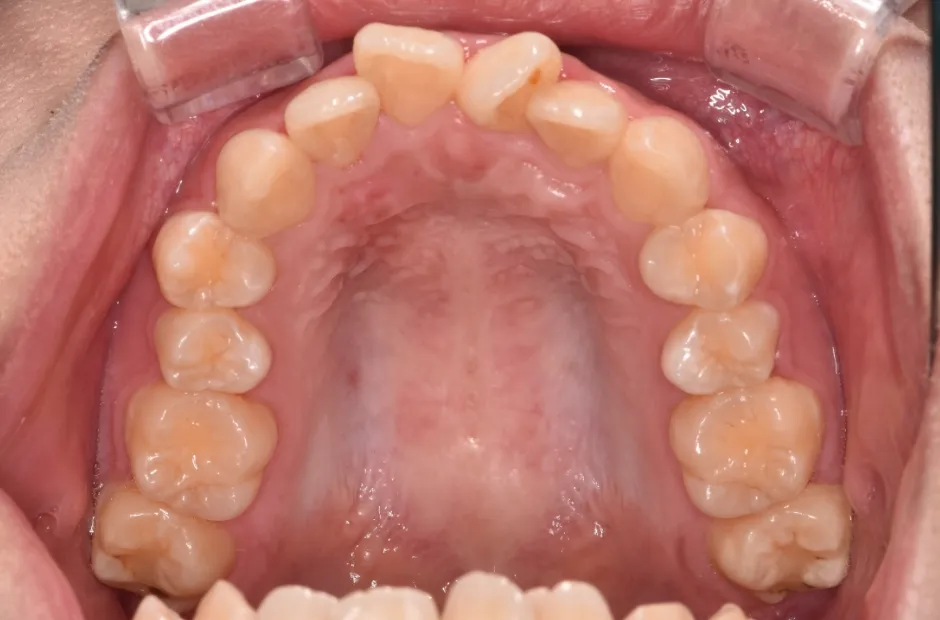

ゆがみ(左右非対称)

| 診断名・主訴 | ゆがみ(左右非対称) |

|---|---|

| 年齢・性別 | 20歳・女性 |

| 治療期間・回数 | 2年半 30回 |

| 治療に用いた主な装置 | 急速拡大 アンカー |

| 抜歯部位 | 左右上5番 |

| 治療費 | 70万円(税抜) |

| リスク・副作用 | 装置による違和感・疼痛・歯肉退縮・歯根吸収・虫歯のリスクなど |

治療前